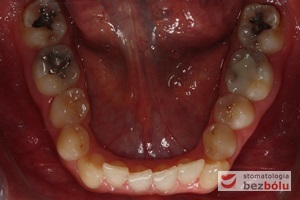

Pacjentka lat 22 zgłosiła się do naszej placówki celem podjęcia leczenia ortodontycznego. Głównym oczekiwaniem pacjentki była poprawa estetyki uśmiechu oraz brak ekstrakcji zębów na drodze do jej uzyskania. Ze względu na liczne stłoczenia zębów w górnym i dolnym łuku, dość duży materiał zębowy w porównaniu z bazą kostną, a także zgryz przewieszony boczny prawostronny po dokładnej analizie cefalometrycznej oraz analizie modeli diagnostycznych zastosowano leczenie bezekstrakcyjne z wykorzystaniem strippingu jako alternatywy dla usuwania zębów, mającego na celu uzyskanie miejsca w łuku na uszeregowanie zębów. Po fazie aktywnego leczenia trwającego 18 miesięcy zastosowano leczenie retencyjne w postaci szyny retencyjnej w łuku górnym oraz retainera stałego w łuku zębowym dolnym klejonego od kła do kła.